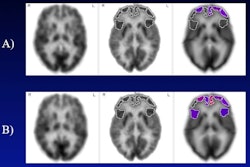

Previous research has suggested that hearing loss is a modifiable risk factor for dementia, Parker and colleagues explained. But the link between hearing, neurodegeneration, and cognitive change remains unclear. Parker's team sought to address this knowledge gap by conducting a study that included information from 287 adults born in the same week of 1946 who underwent baseline pure tone audiometry and cognitive assessment/multimodal brain MRI exams at two different time points. The group defined hearing impairment at baseline as a pure tone average of greater than 25 decibels in the best hearing ear; estimated rates of change for whole brain, hippocampal, and ventricle volume from the MRI exams; and assessed study participants' cognition using the Pre-clinical Alzheimer's Cognitive Composite tool.

Of the 287 participants, 111 had hearing impairment. The authors found that, compared with those who did not have hearing impairment, those who did had faster rates of whole-brain atrophy (p = 0.031). It also found that worse hearing (that is, higher pure tone average) predicted faster rates of hippocampal atrophy and that faster rates of whole brain atrophy translated to greater cognitive changes (p = 0.004). Both these results remained after the team adjusted for adjustment for amyloid beta status and white matter hyperintensity volume, the team wrote.

"[Peripheral] hearing impairment predicts faster rates of brain atrophy in older adults," it noted. "This is consistent with previous reports, but extends these findings to show these effects are independent of [amyloid beta]-status and [white matter hyperintensity volume], suggesting that relationships between hearing loss and neurodegeneration may be driven by mechanisms other than Alzheimer's or cerebrovascular disease."